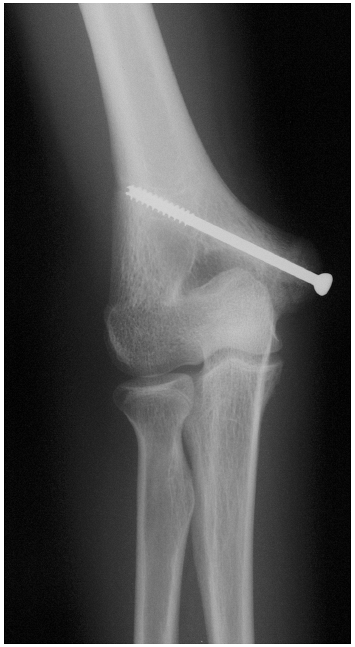

Radiographs demonstrate a variable amount of medial epicondyle displacement (Fig. 5-4).

Avulsions larger than 1 cm are repaired with pins or 3.5-or 4.0-mm cannulated screws and direct repair of the UCL if torn (Fig. 5-5).

Figure 5-4

Radiograph demonstrating medial epicondyle avulsion. Comparison films may be necessary. Early repair permits immediate motion and may decrease stiffness and permit faster recovery. |

Figure 5-5 Repair of medial epicondyle avulsion with 4.0-mm cannulated screw.

|